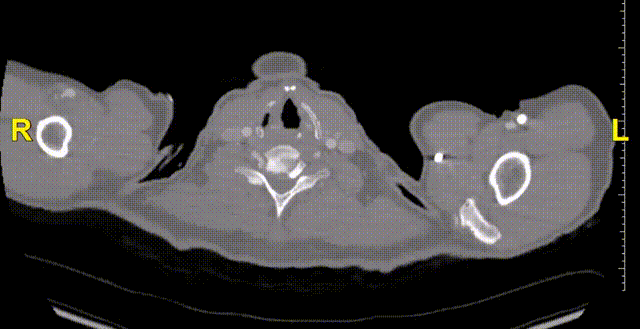

现病史:患者7小时前无明显诱因出现腹部胀痛不适,以下腹部为主,无发热、恶心、呕吐,无头晕、头痛等特殊不适,因症状持续不缓解,遂来我院急诊就诊,行腹主动脉(下腹部、盆腔段)CTA示:腹主动脉下段,右侧髂总动脉动脉瘤形成,右侧巨大髂总动脉(直径85.0mm*77.1mm)有明显造影剂溢出提示破裂,腹主动脉周围、左侧肾周、左侧腰大肌前缘及骶前积血较前明显增多,于急诊抢救室出现一过性意识丧失、血压下降休克状态,予积极补液后症状好转,现为进一步治疗,急诊以“腹主动夹层动脉瘤;髂动脉巨大动脉瘤破裂”收入院。

术前诊断:腹主动脉夹层,髂动脉瘤破裂,失血性休克。

二、术前CTA详解